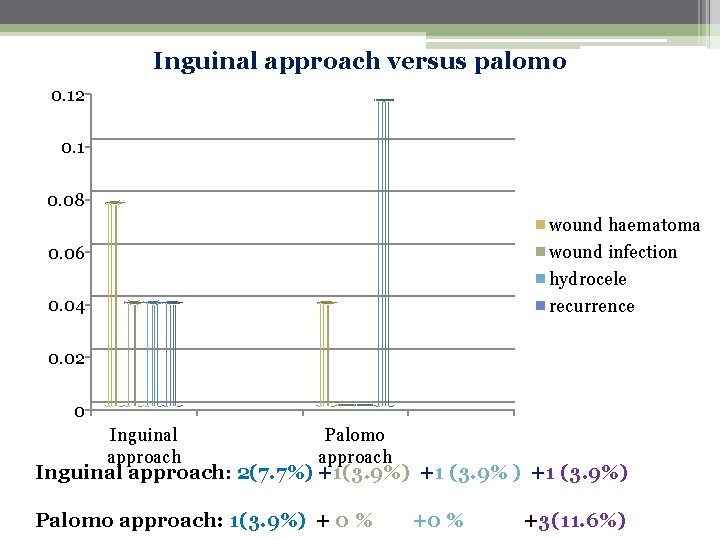

Varicocele management A comparison of Palomo versus Inguinal approach 2009 Patient and Methods: 52 patients were included in study. Randomly 26 patients were Operated In each group i. e inguinal and palomo. All patients were followed at 3 and 6 months and 1 year. The results were ……………

Inguinal approach versus palomo 0. 12 0. 1 0. 08 wound haematoma wound infection hydrocele recurrence 0. 06 0. 04 0. 02 0 Inguinal approach Palomo approach Inguinal approach: 2(7. 7%) +1(3. 9%) +1 (3. 9%) Palomo approach: 1(3. 9%) + 0 % +3(11. 6%)

Conclusion It is concluded the palomo operation Is better than inguinal approach for varicocelectomy. There is decreased complication rate and better Patient satisfaction. However recurrence is less in inguinal approach. Both Procedures improve fertility. however choice of procedures seems to be More of surgeon, s training and personal liking Than considering benefits and draw backs of both procedures.